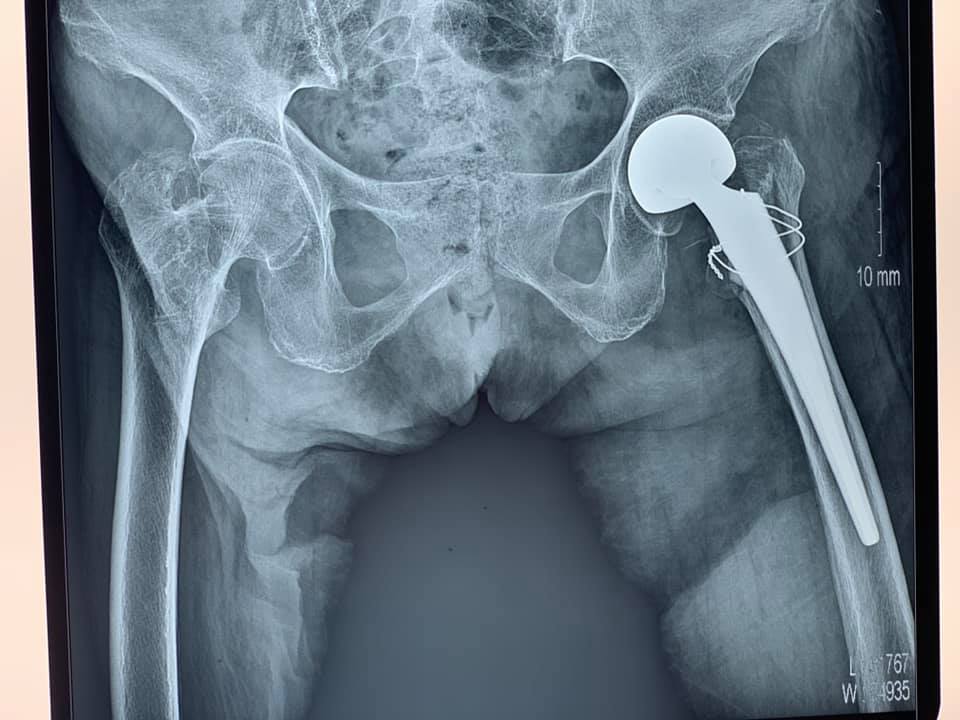

Gần đây nhất là trường hợp cụ bà Trần Thị C, 101 tuổi, ở Đông Quang – Ba Vì – Hà Nội bị gãy kín Liên mấu chuyển xương đùi trái do ngã ngày thứ nhất, bệnh nhân có bệnh lý tim mạch, tăng huyết áp, thiếu máu, suy kiệt.

Tiến hành làm các xét nghiệm, siêu âm, chụp X- quang, các bác sĩ nhận định đây là một trường hợp cần được phẫu thuật sớm, có thể cho bệnh nhân sớm ngồi dậy, tập luyện để tránh các biến chứng. Chỉ sau 1 ngày, bệnh nhân được phẫu thuật thay khớp háng trái nhân tạo bán phần không xi măng. Vượt qua những khó khăn trước phẫu thuật do tình trạng sức khỏe chung và bệnh lý nền kết hợp của bệnh nhân, kíp phẫu thuật đã kết hợp với kíp gây mê tiến hành thành công ca phẫu thuật, giúp cho người bệnh có cơ hội sớm bước đi trở lại.